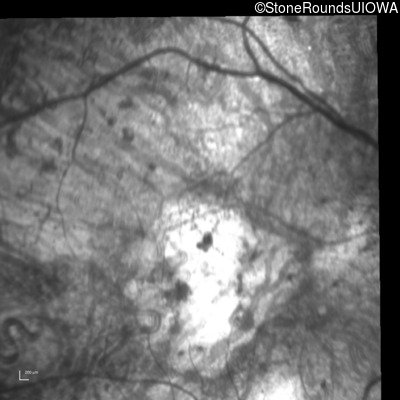

Infrared Fundus Photograph - Left - Hand Motion 6" sc

Exemplar